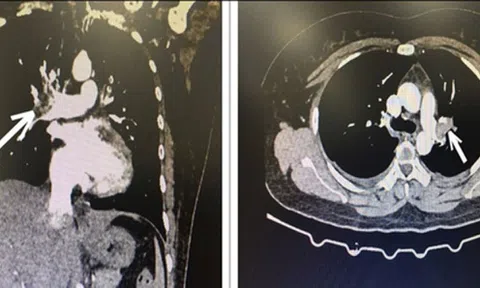

Phải cấp cứu vì uống 15 viên thuốc tránh thai mỗi tháng suốt 10 năm

Người phụ nữ 34 tuổi liên tục dùng thuốc tránh thai khẩn cấp suốt 10 năm, mỗi tháng trung bình 12 - 15 viên, khiến động mạch phổi bị tắc.